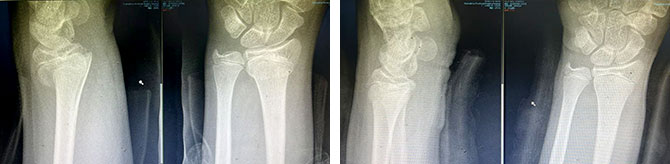

儿童桡骨远端骨折(伸直型)

复位前 复位后